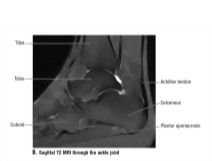

Sagittal T2 MRI Through the Ankle Joint